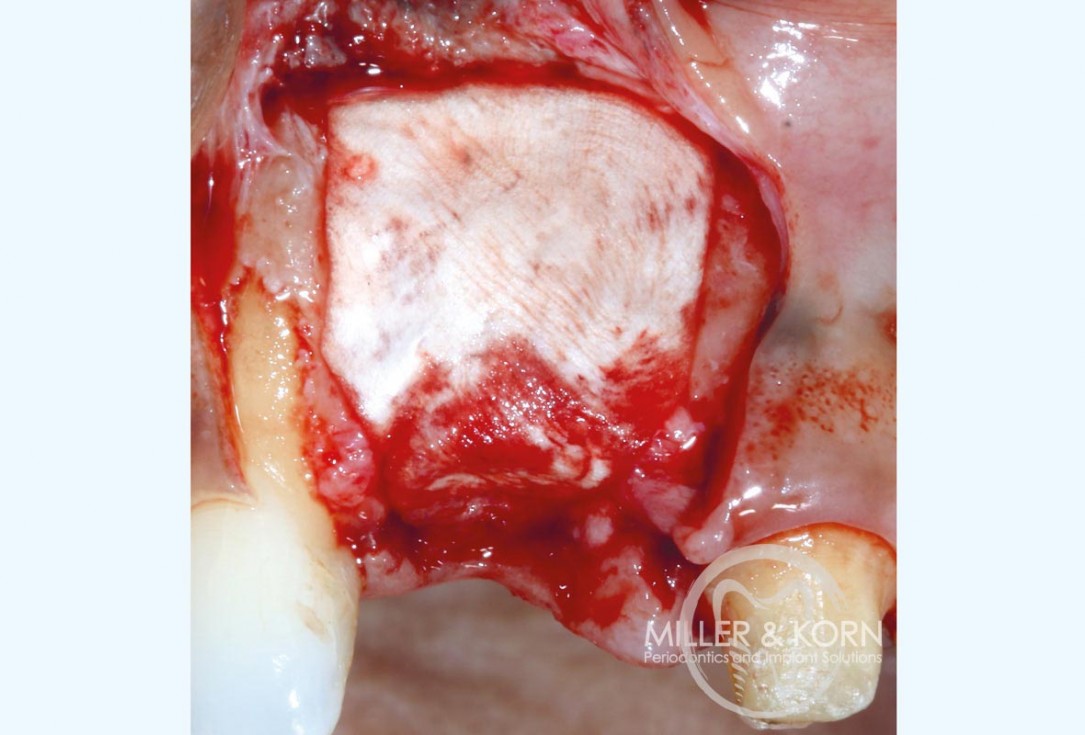

8/22 - Use of the planator to create a uniform ring bed.Immediate implant placement and regeneration of ridge using an allograft bone ring and Jason® membrane - Drs. Miller and Korn

9/22 - Occlusal view of the prepared recipient ring bed.Immediate implant placement and regeneration of ridge using an allograft bone ring and Jason® membrane - Drs. Miller and Korn